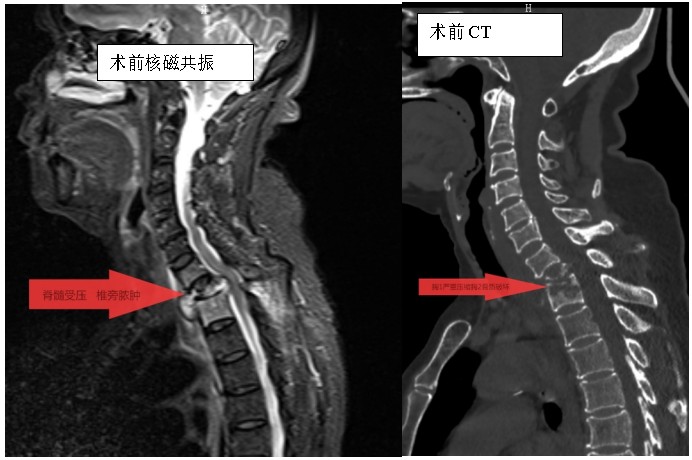

家住耒陽的70歲的李奶奶,因“頸胸背部疼痛不適伴雙上肢麻木6個月”,來到衡陽市中心醫(yī)院脊柱外科住院,住院當(dāng)天,患者頸胸椎核磁共振顯示:胸1、2椎體骨質(zhì)破壞,伴胸1、2椎旁軟組織腫脹、同層面椎管變窄,因脊髓受壓而導(dǎo)致頸胸背部疼痛。在錢軍博士帶領(lǐng)下,醫(yī)療團隊詳細予以完善相關(guān)檢查后,研究患者的臨床資料,考慮脊柱結(jié)核并椎旁膿腫的可能性大,由于患者胸1椎體病理性骨折并椎管狹窄,遂囑患者嚴(yán)格臥床休息,術(shù)前給予標(biāo)準(zhǔn)四聯(lián)抗結(jié)核藥物治療2周,以控制活動性結(jié)核感染,降低術(shù)中播散風(fēng)險,并嚴(yán)密監(jiān)測肝腎功能及血常規(guī)情況。

錢軍博士組織團隊進行了詳盡的術(shù)前討論,充分的術(shù)前準(zhǔn)備后,于8月10日為患者實施了“前路病灶清除、人工椎體植入、植骨融合內(nèi)固定術(shù)”。順利完成了徹底清除病灶,椎管減壓解除脊髓壓迫,矯正后凸畸形,重建脊柱穩(wěn)定性的手術(shù)目標(biāo)。